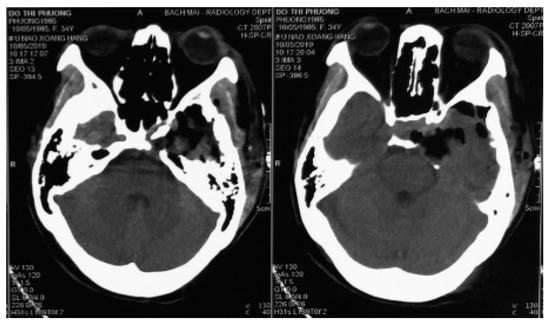

A 34-year-old female presented with a history of occassional headache without remarkable physical and neurological symptoms. Routine laboratory investigations and pituitary hormonal tests were all normal. She was taken for a magnetic resonance imaging and a mass was discovered in the region of the sellar and left parasellar. The size of the lesion was around 30 mm. It elicited a high signal on T1-weighted and T2-weighted images, strong enhanced gadolinium, and a homogenous intense surrounding left cavernous internal carotid, pushing downward on the skull base and pushing the pituitary contralaterally (Figure 1).

Figure 1.

Contrast-enhanced magnetic resonance imaging examination of the brain. (a,b) Pre contrast coronal and sagital T1w showed an extra axial sellar and left parasellar mass with hyperintensity, the cavernous internal carotid artery is pushed inferiorly and encased by the lesion. (c) Coronal T2w showed a high signal intensity of the mass. (d) Initial gadolinium-enhanced axial T1w showed heterogenous enhancement of the mass.

In the magnetic resonance imagings, the lesion revealed an enhanced homogenous mass encircling the cavernous segment of the internal carotid artery without occluding it. This might be related to the natural character of the tumor. With cavernomas in the cavernous sinus, the blood stream through the lesion was homogenous, contrary to cavernomas intracerebral parenchyma, with no bleeding inside the tumor, and no calcification. Cerebral cavernomas appeared as “popcorn-shaped” or “berry-shaped”, which showed isointense in magnetic resonance imagings with a rim of signal loss due to hemosiderin. This was a specific radiological feature of parenchymal cavernomas, but it seldom happens with extra axial cavernomas, especially in the cavernous sinus [7]. In the magnetic resonance imaging, CSCs were homogenous; hyperintense in T1w, T2w, and T2 Flair; showed contrast enhancement; and rarely had intratumor bleeding or calcification (Figure 1).